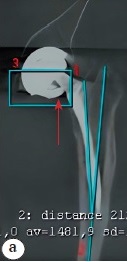

Multi-slice computed tomography (MSCT) revealed head decentration. Its correct shape was visualized, which only enabled us to assume its integrity; and a freely lying fragment of a ceramic liner in the neck area of the femoral component was noted. The retroversion was 23° with acetabular component malposition (Fig. 3).

Fig. 3. MSCT: a — frontal projection: decentration of the femoral component head, its correct shape and a fragment of the ceramic liner in the area of the femoral component neck (arrow) are visualized; b — axial projection: malposition of the acetabular component on the left — 23° retroversion